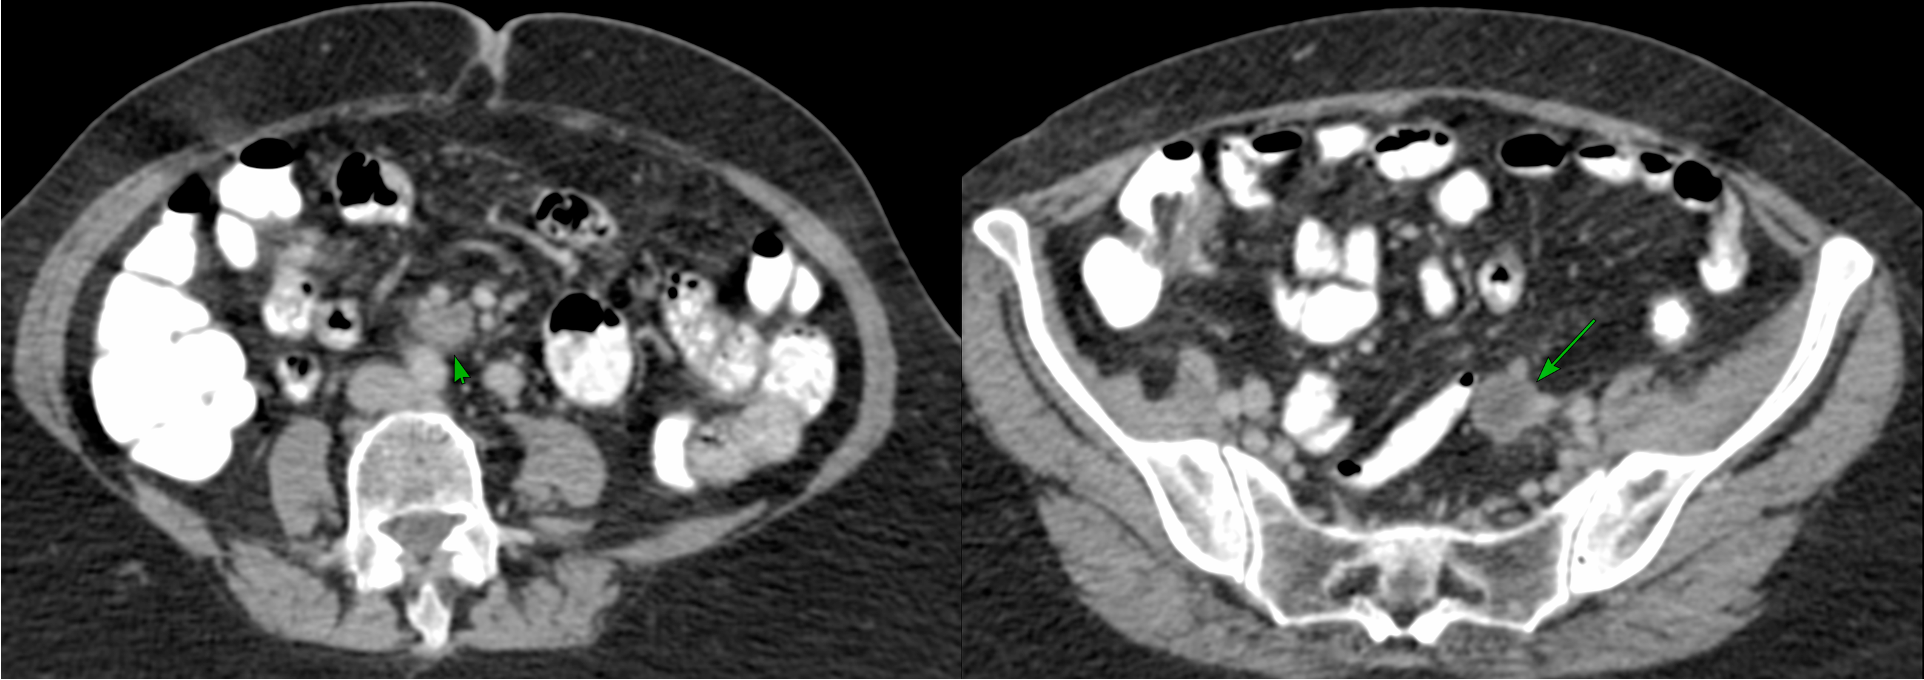

A 69-years old treated earlier for carcinoma ovary and endometrium, presented with new mesenteric nodules/nodes.

The oncologist wanted a biopsy.

This node/nodule and approach seemed to be the best bet.